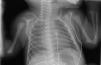

Recién nacido a término que, a los diez minutos de vida, comienza con distrés respiratorio que disminuye tras su ingreso en Neonatología con oxigenoterapia mediante gafas nasales. A la exploración física: hipoventilación bilateral sin otros hallazgos patológicos. Se realiza radiografía anteroposterior de tórax sin alteraciones patológicas (fig. 1), por lo que se decide realizar ecografía pulmonar, visualizándose neumotórax anterior bilateral (fig. 2). En ella se observa ausencia de deslizamiento pleural con signo del punto pulmonar en modo B en línea axilar anterior y el signo del «código de barras» o de la «estratosfera» en modo M (flecha), que indica ausencia de deslizamiento pleural. Por motivos didácticos, se decide realizar una radiografía de tórax lateral con rayo horizontal, confirmándose el hallazgo (fig. 3, flecha negra). El paciente evoluciona de manera favorable, pudiéndose retirar la oxigenoterapia a los dos días de ingreso. Durante ese tiempo se realizan controles seriados ecográficos hasta confirmar resolución de manera espontánea.